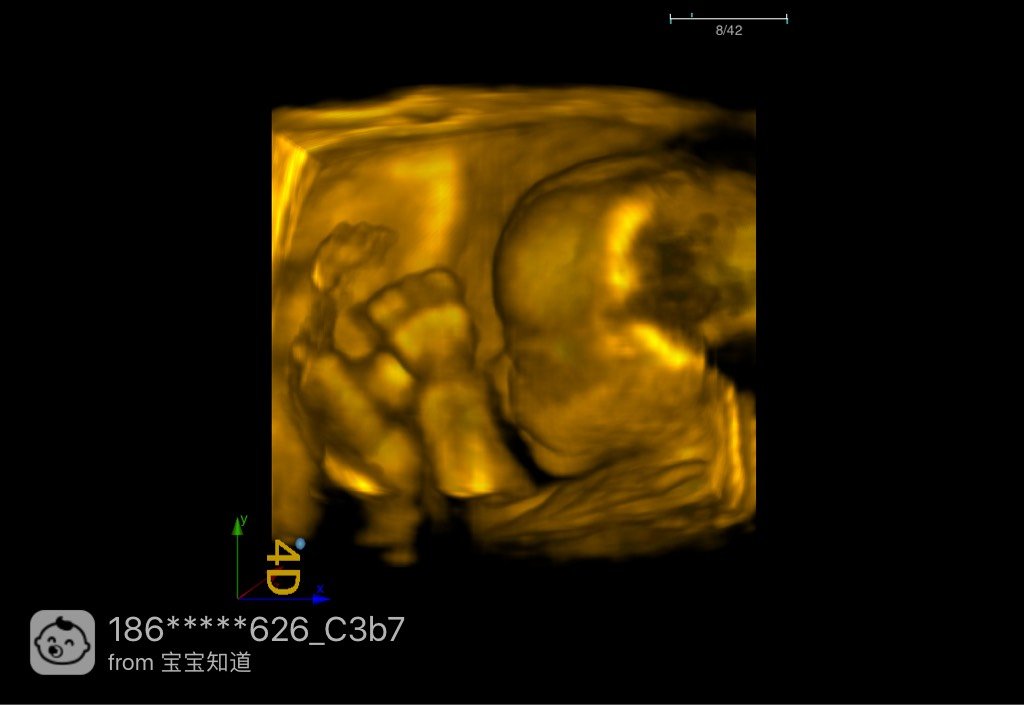

照了四维有会看男女的吗?

四维彩超照完了,关键部位医生也拍了,但是还是锈侨不会看实浅今,有没有会看的团肆宝妈

男宝

24+3周